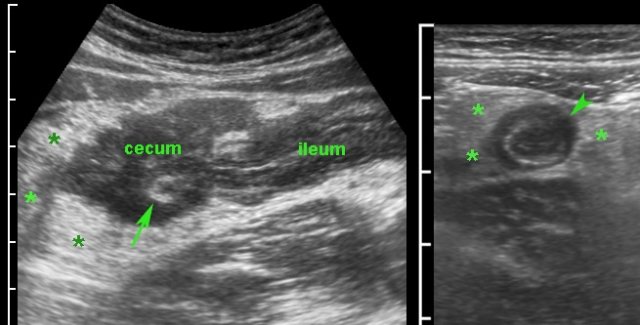

Classic US features of right-sided infectious ileocolitis in a young man.

Prominent mucosal and submucosal wall thickening of terminal ileum and right colon, enlarged inflamed mesenteric lymph nodes and a normal appendix.

Note the prominent ileocecal valve, due to both wall thickening of ileum and cecum in this patient with right-sided Campylobacter ileocolitis.

Typical, prominent image of the ileocecal valve in infectious ileocecitis due to (sub)mucosal thickening of both ileum and cecum.

The ileocecal valve is visualized in two planes, perpendicular to each other (note body scheme).

As clinically observed in Campylobacter patients, pain in Campylobacter ileocecitis is often intermittent and crampy in nature.

During these crampy pain attacks (remember “Crampylobacter”), the ileum is slightly intussuscepted into the cecum, sliding back again after the attack.